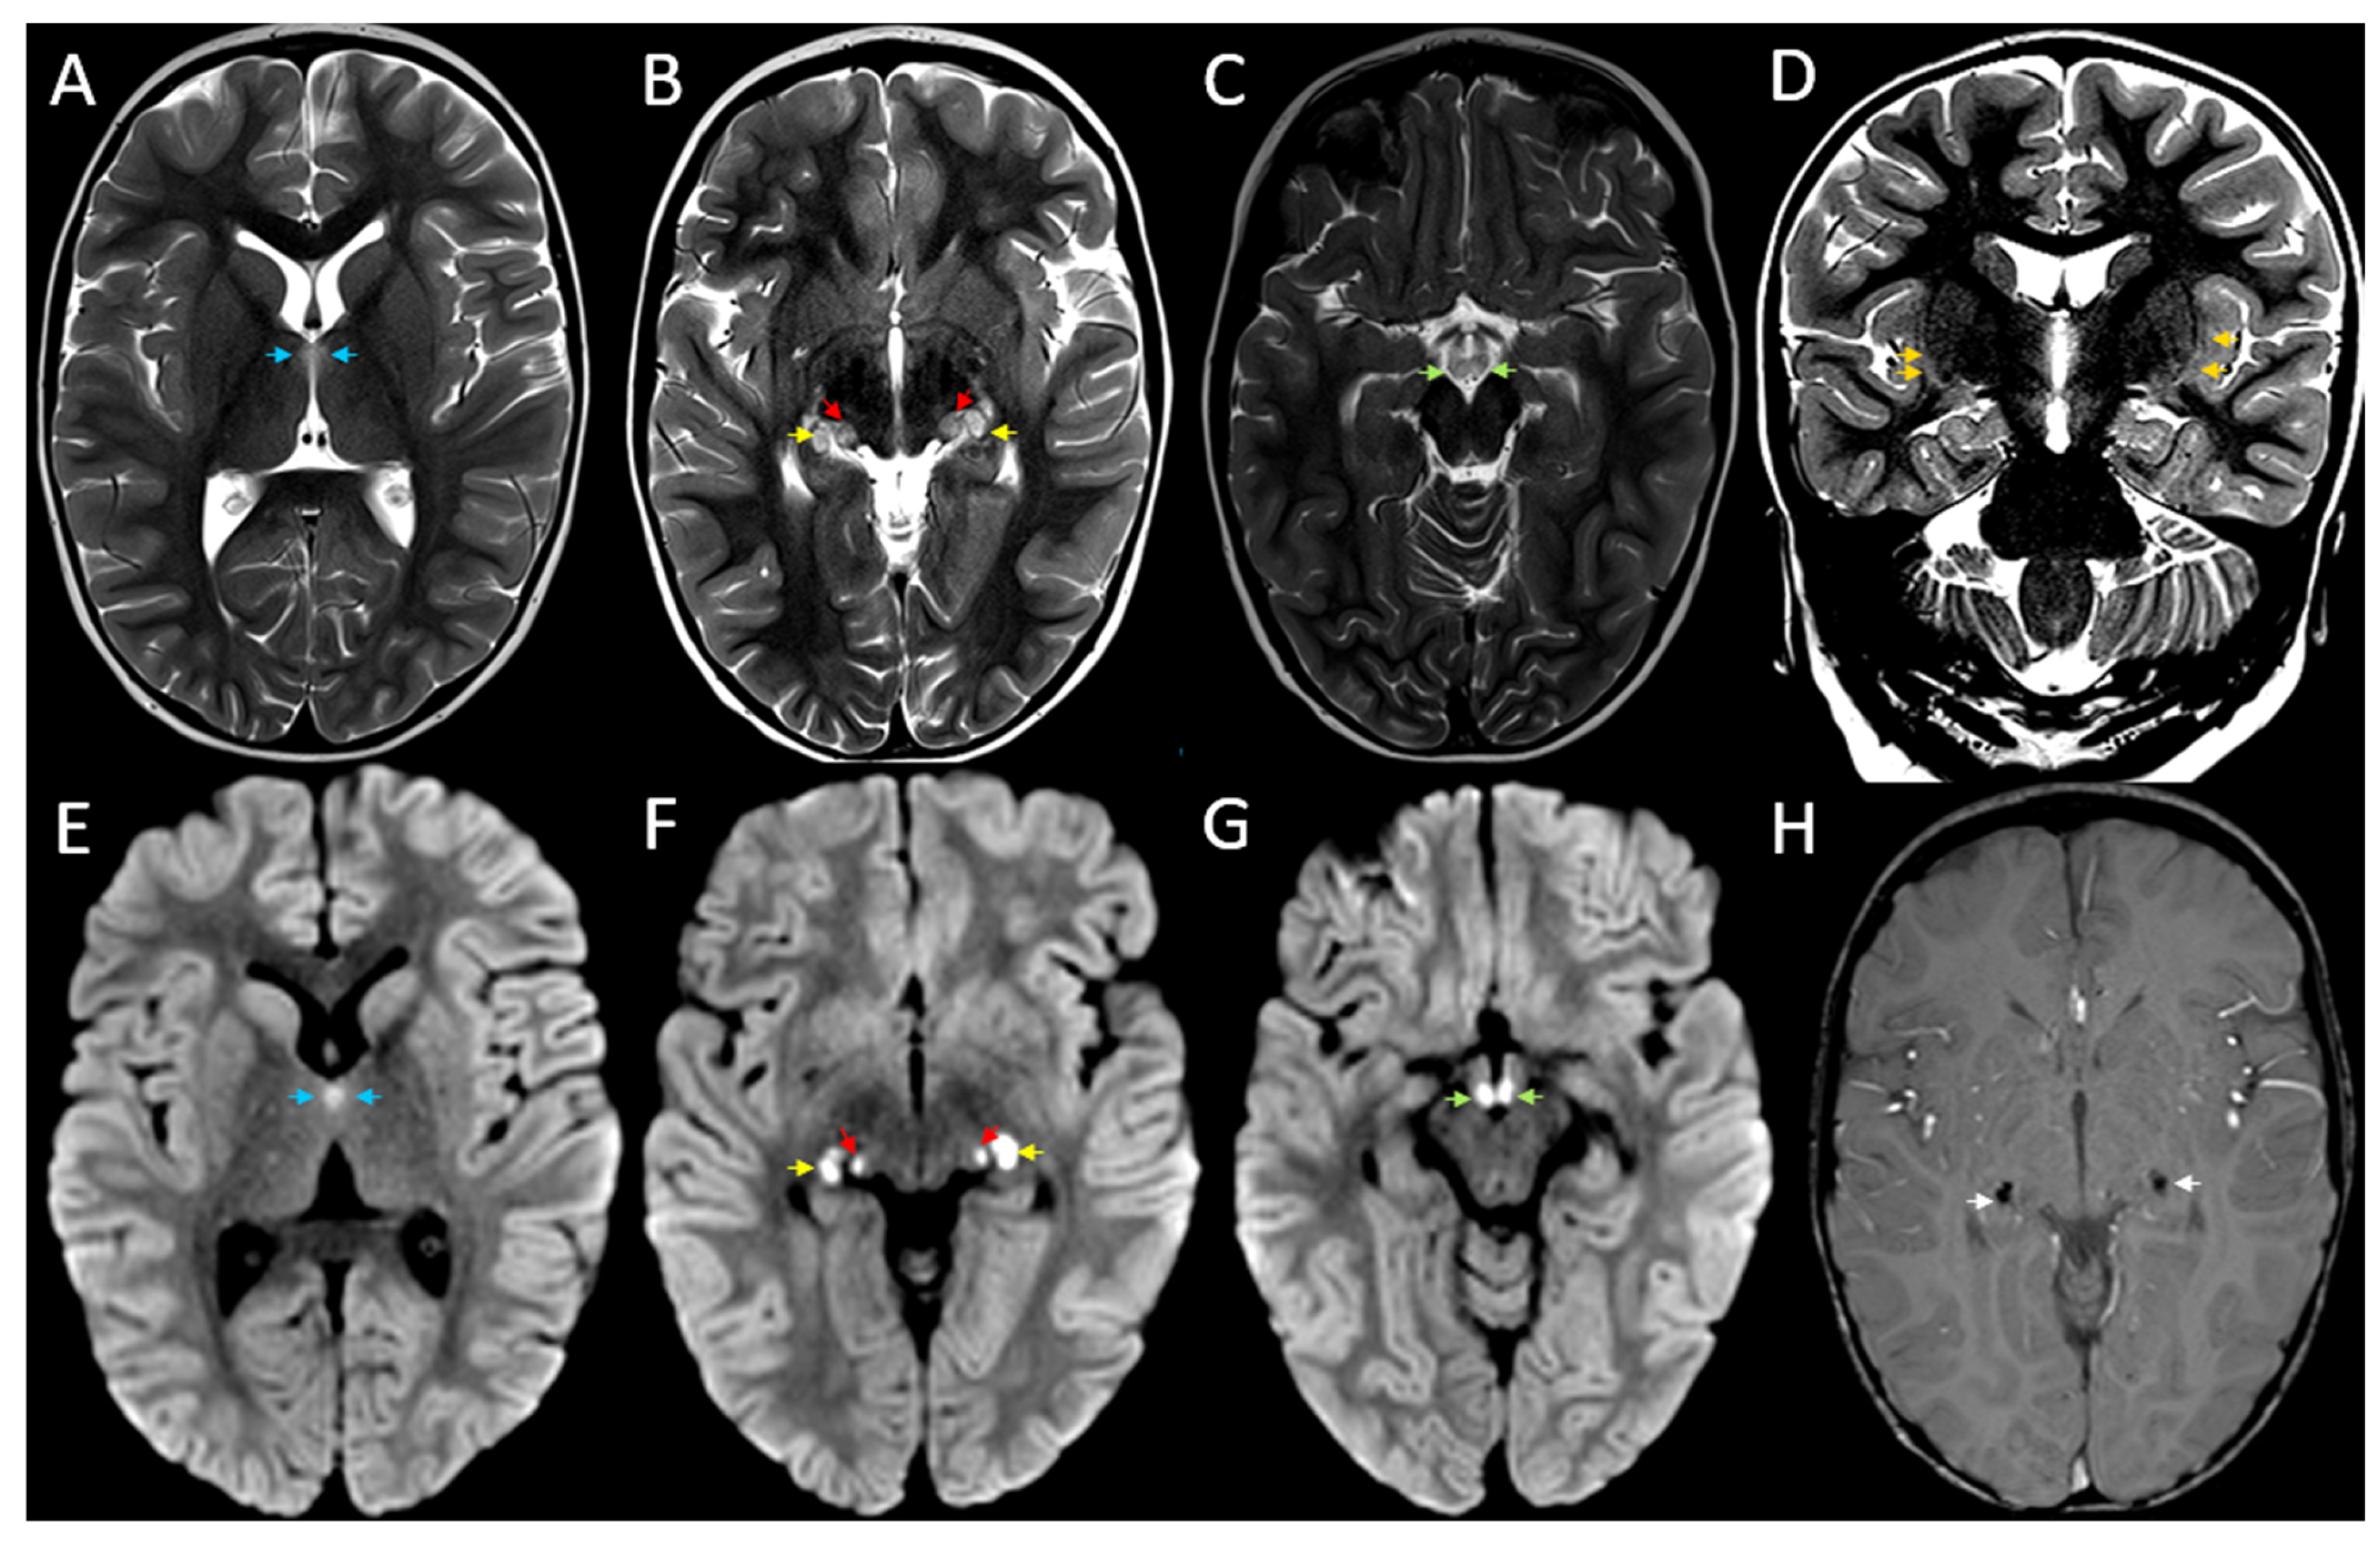

Bilateral Symmetrical Brain MRI Findings in Acute Necrotising Encephalopathy Type 1